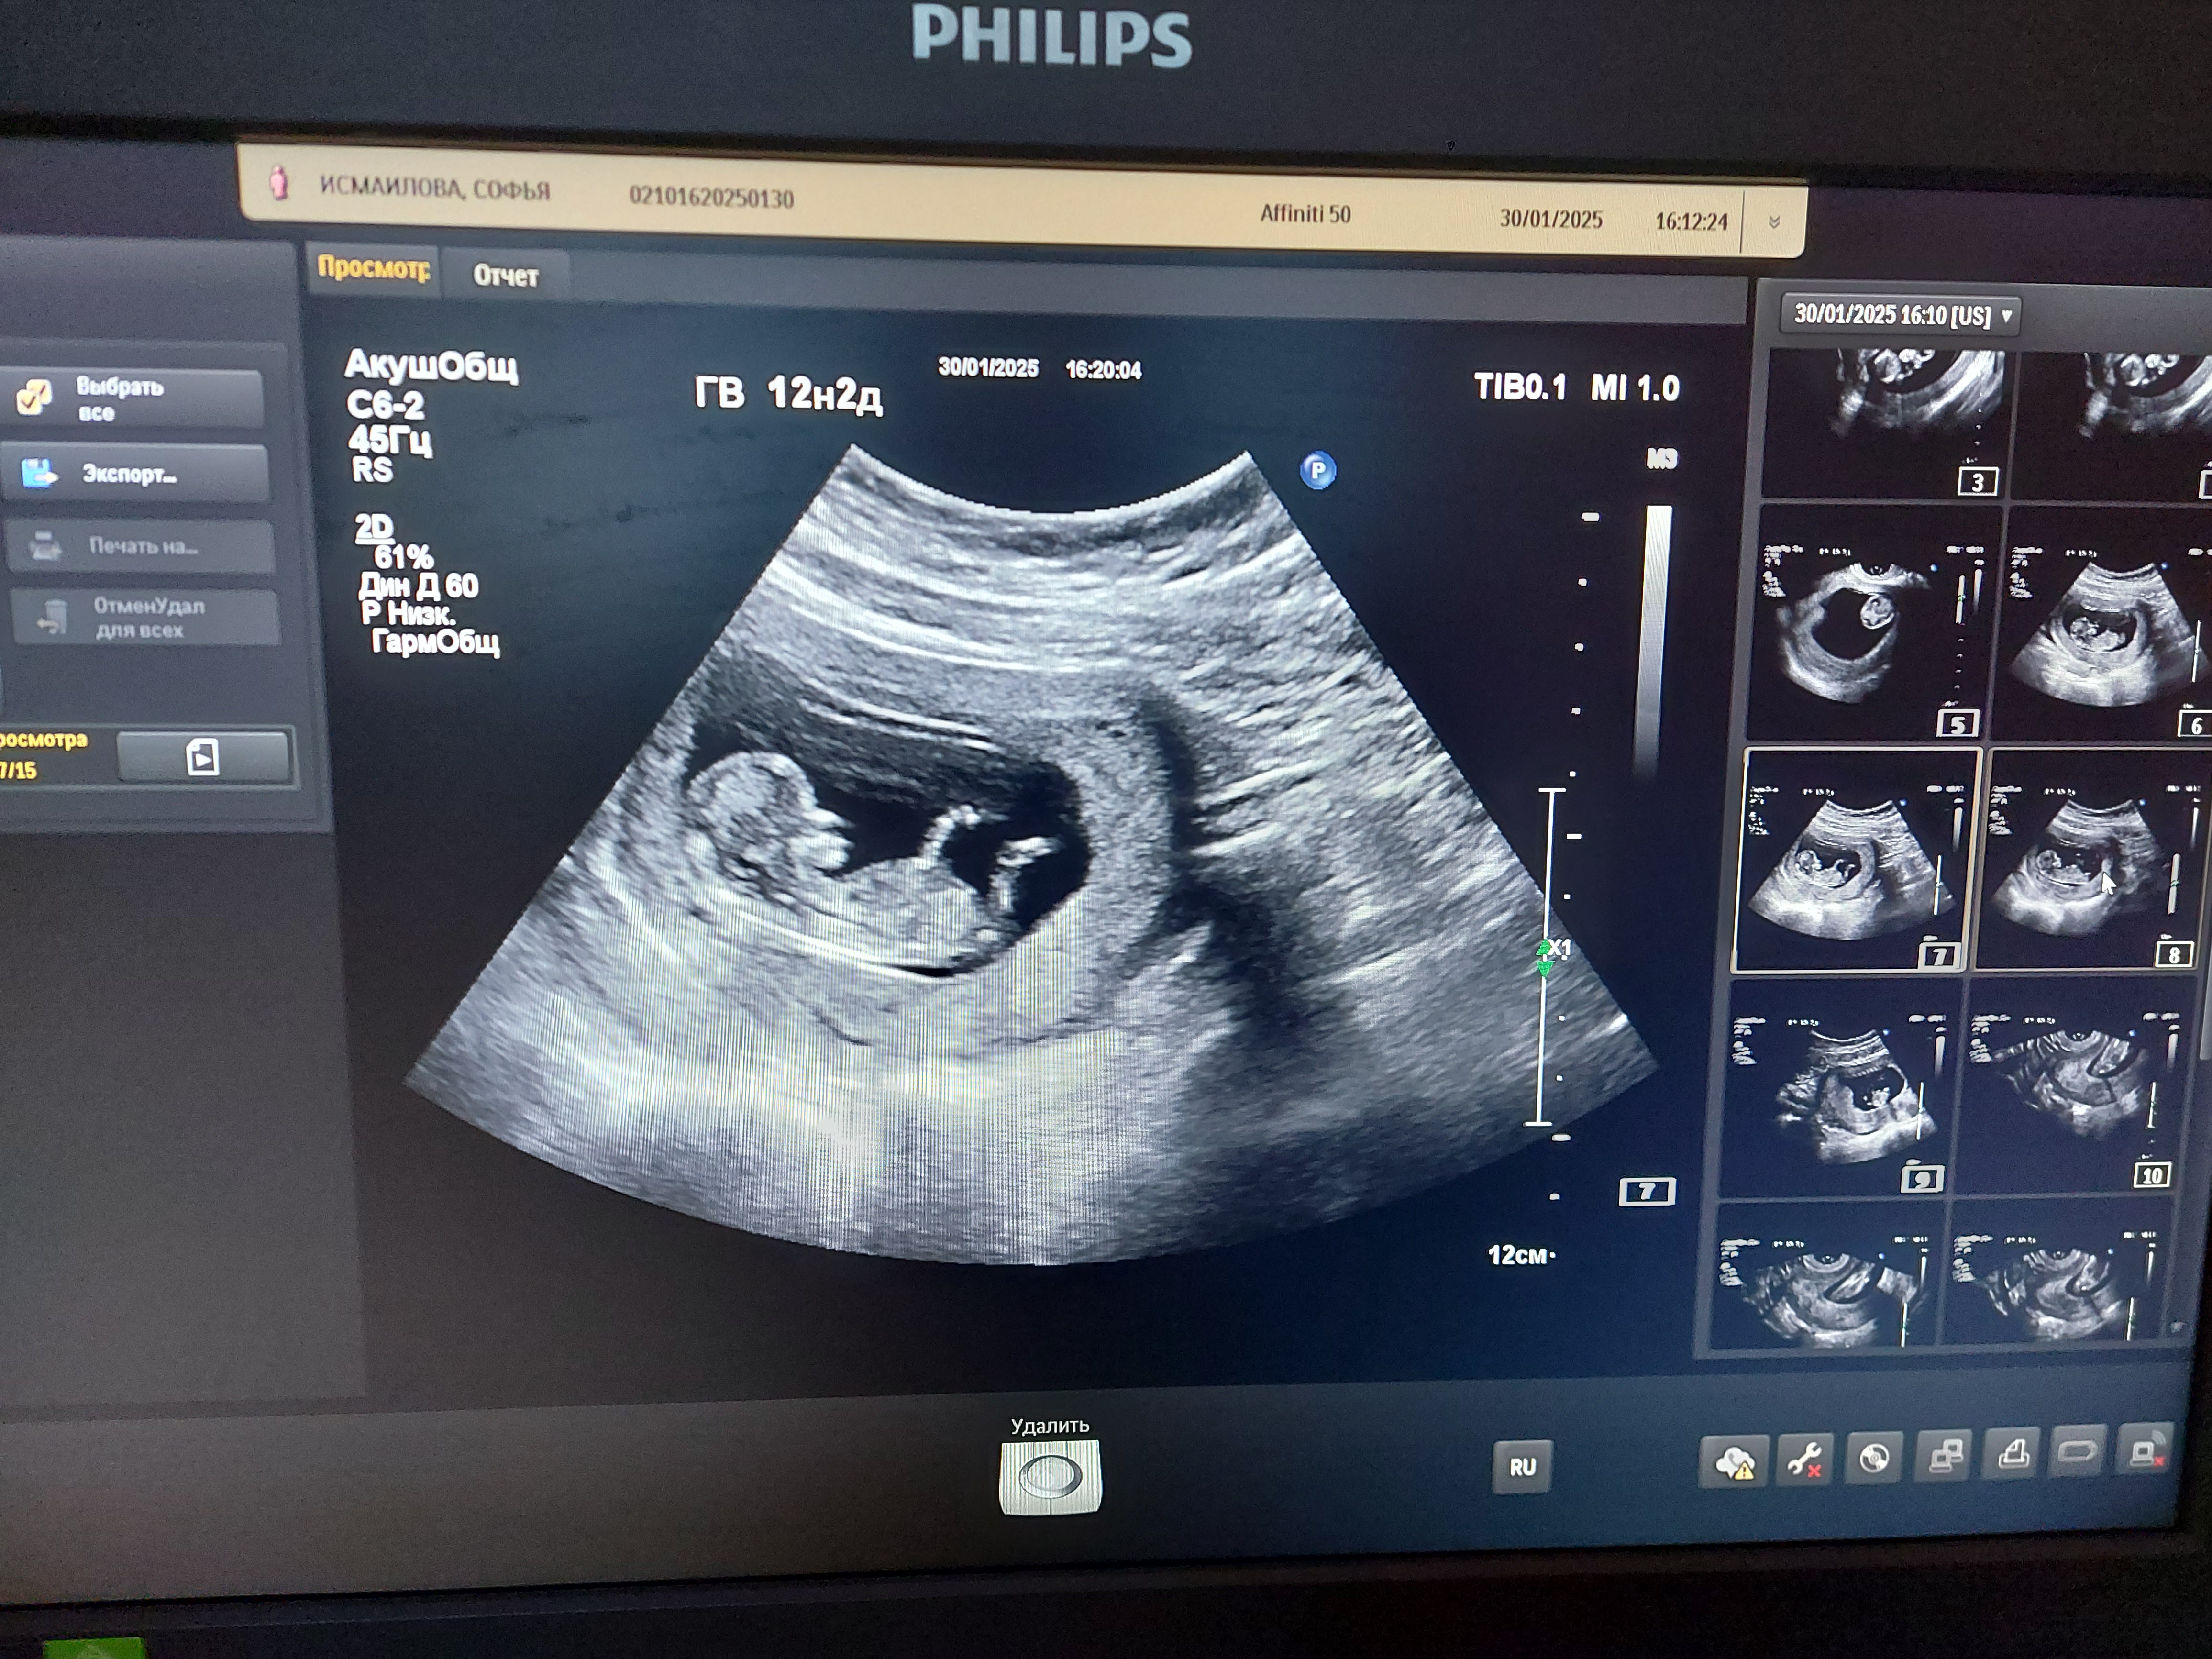

Мальчик или девочка

Ставлю на девочку)

Вроде и угол не большой, можно было девочку увидеть, но мне, по расположению писюнчика относительно мочевого пузыря (если это точно он на снимке😅), кажется, что мальчик🩵

Мне кажется, что мальчик

Думаю, что мальчик у вас💙

Мне кажется, что девочка.

Мальчик явно 💙

Малышарик прячется Определение пола на 15 неделе